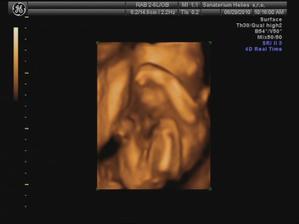

29.6. jdeme na 3D ultrazvuk 🙂 těšíme se... - bylo to úžasný 🙂 cena sice vyšší, ale jedna barevná fotka tištěná, 3 fotky na mail a téměř půlhodinové video, ze kterého jsme si doma udělali ještě asi 120 fotek 🙂